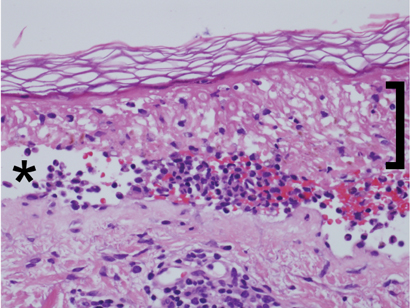

Histopathological examination (Box 3) showed extensive epidermal necrosis and subepidermal clefting with a sparse superficial perivascular infiltrate of lymphocytes, occasional neutrophils and eosinophils, and exocytosis of cells into the epidermis. Results of staining for immunofluorescence were negative. This was consistent with the clinical diagnosis of TEN, and the possibility of pemphigus vulgaris was excluded.